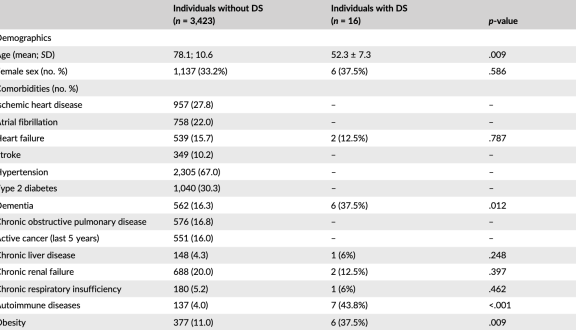

di Valeria Caramello, Adriana Boccuzzi, Carlotta Sacerdote, Fulvio Ricceri